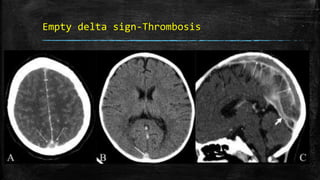

Empty delta sign-Thrombosis

▪ Hyperdense subarachnoid hemorrhage, subdural empyema, or

hematoma surrounding the sinus may result in the ‘pseudodelta’ sign

on unenhanced CT scan.

• #67 Empty delta sign. Postcontrast axial CT scan of the brain (A) shows the nonenhancing lumen of the superior sagittal sinus surrounded by enhancing dura (arrows). Nonenhanced axial CT scan of the brain (B) shows a hyperdense superior sagittal sinus (arrow) suggestive of thrombus within. This is called the ‘triangle sign.’ Sagittal reconstruction of a contrast-enhanced CT scan (C) shows filling defects in the superior sagittal sinus (long arrows) and in the straight sinus (thick arrow), suggestive of thrombus